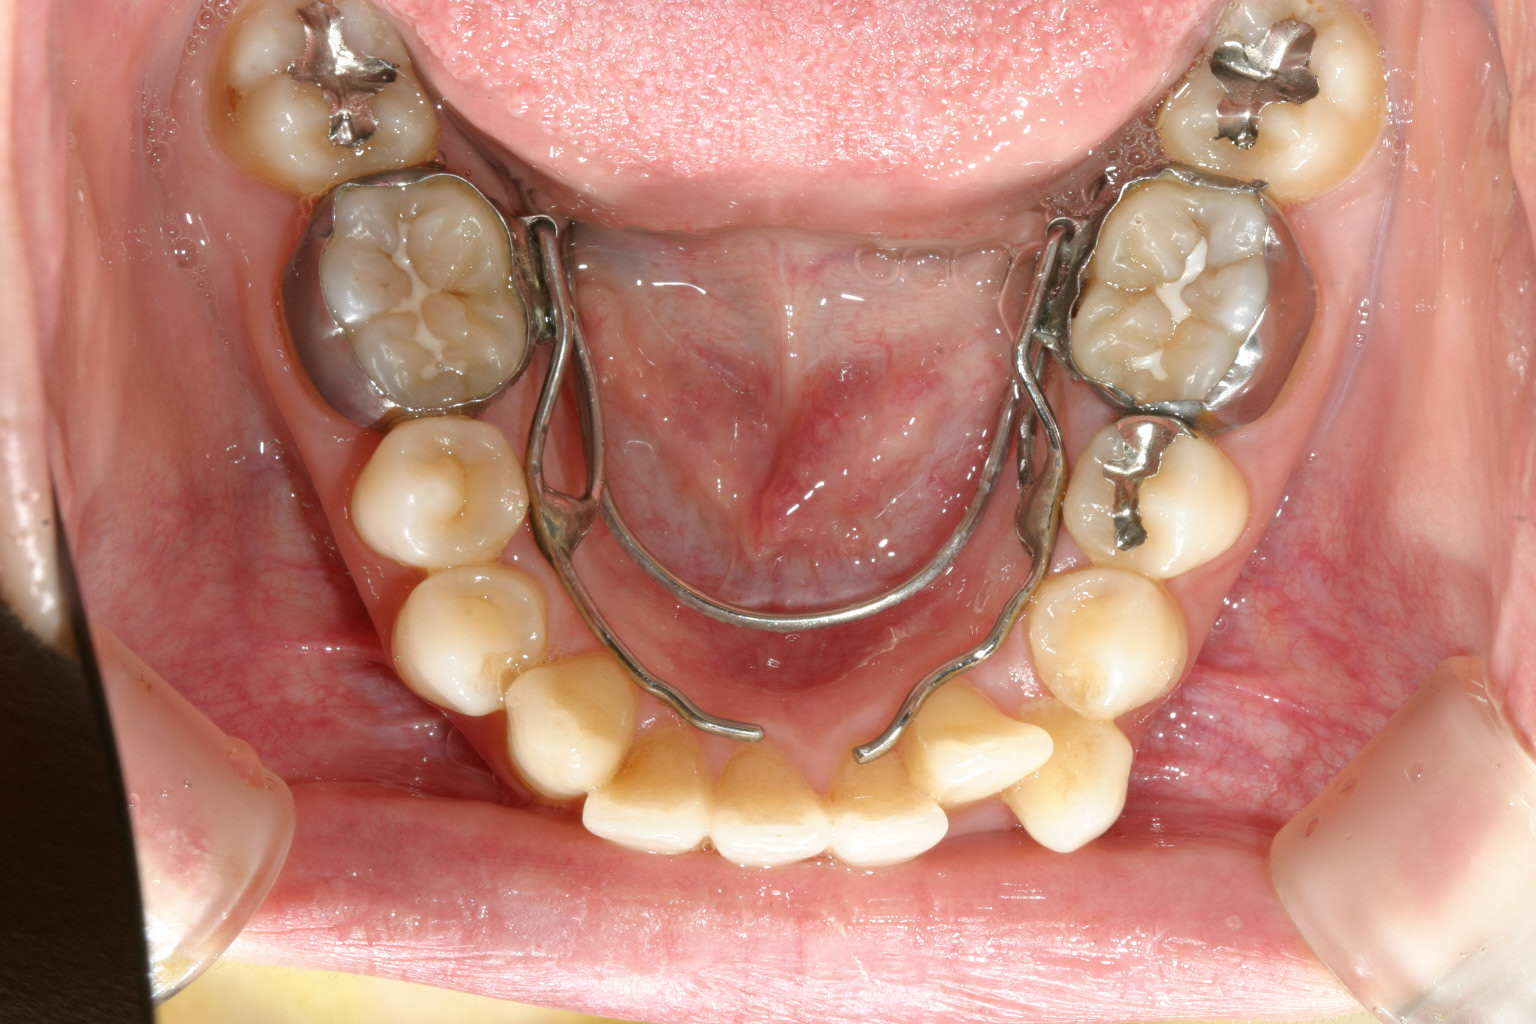

インビザライン初期はこの様な装置でアーチを拡大してからインビザラインを使用していた時期もありました。 現在はこの様な装置は使っていませんが!

特に下顎のアーチが狭い為にクワッドヘリックスって言う装置を使って拡大しています。 現在はインビザラインも進化しこの様な装置を使わずインビザライン単独で拡大できるようになりました。